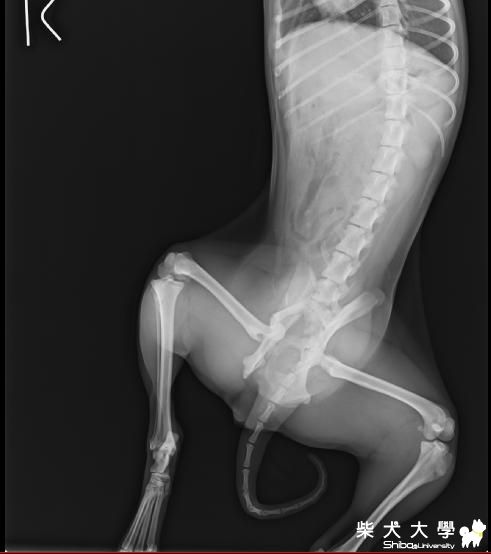

[醫療保健]骨盆骨折手術後 會有哪些後遺症(原發表者:天生神準)

目前竹筍已經手術完了還待在醫院吊點滴

預計明天要去帶他回來 自行照顧

竹筍還年輕 骨折的地方有拉回來接上了

有些地方還碎裂了

這樣他以後能正常走路嗎